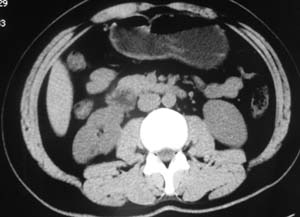

以下是引用子期在2010-3-19 20:47:00的发言:[br]血管畸形的ct增强应该有明显强化,本例并不相符合。本例双肾局部的略低密度影,累及肾盂,局部皮质明显变薄、内陷,增强扫描有轻度的强化,应考虑为炎性病变,患者为年轻男性,累及双肾的感染以结核较常见,可以没有明显的临床症状,尿中有时候也并不能查出什么;肾脓肿常有明显感染中毒症状,本例不符,另外一般的肾盂肾炎或肾小球肾炎通过小便就可确诊,其它还不能排除的是黄色肉芽肿性肾盂肾炎,然而单凭ct一般也很难鉴别。